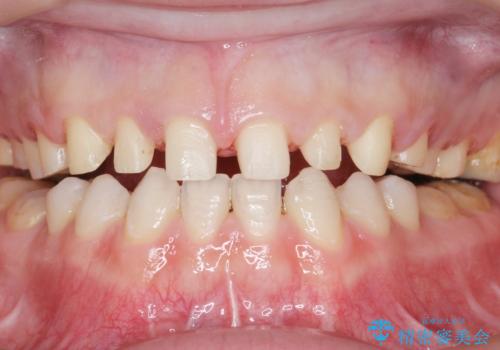

- K-POP(Kポップ)アイドルのような歯にしたいと希望され来院された患者様です。

矯正を途中でやめてしまったとのことで、歯に矯正の接着材が残っており着色も顕著でした。

奥歯の咬合面にはレジンが盛られた状態でした。

見た目と咬み合わせを改善するため、セラミッククラウンによる治療を行いました。

下顎はホワイトニングを行っております。